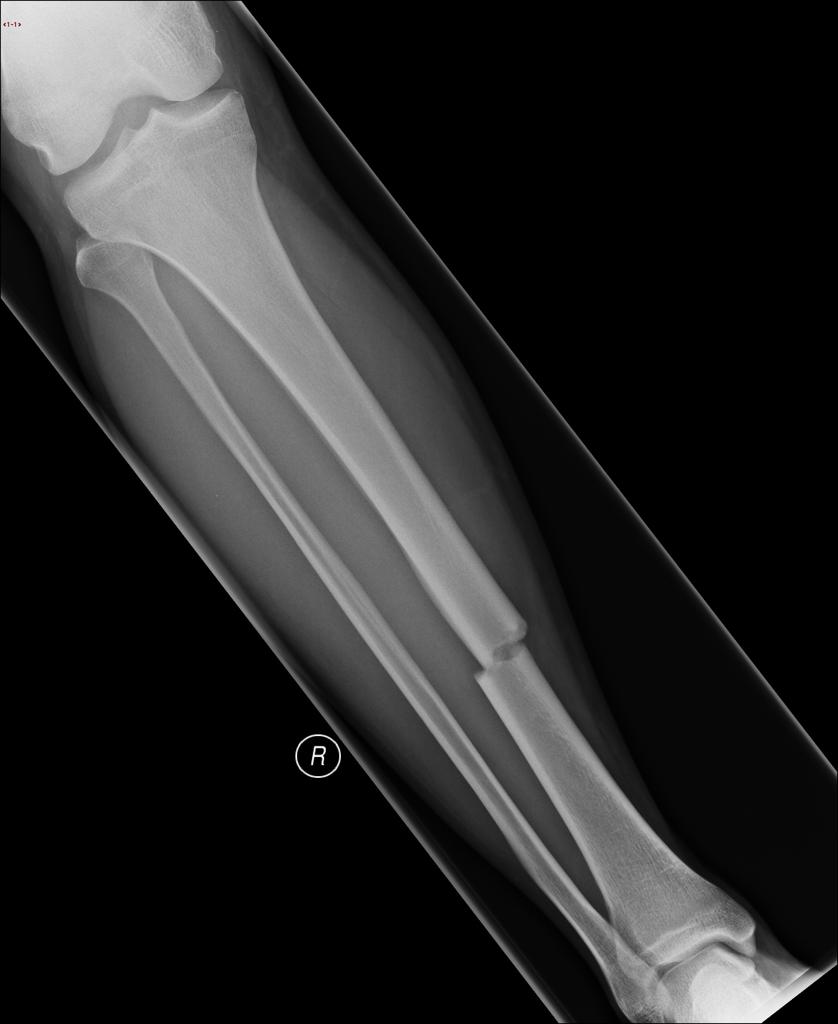

Example 4

Diagnosis

Tibial Midshaft Fracture

Image 4: Sorrentino, S. Tibial midshaft fracture. Case study, Radiopaedia.org. https://doi.org/10.53347/rID-15121